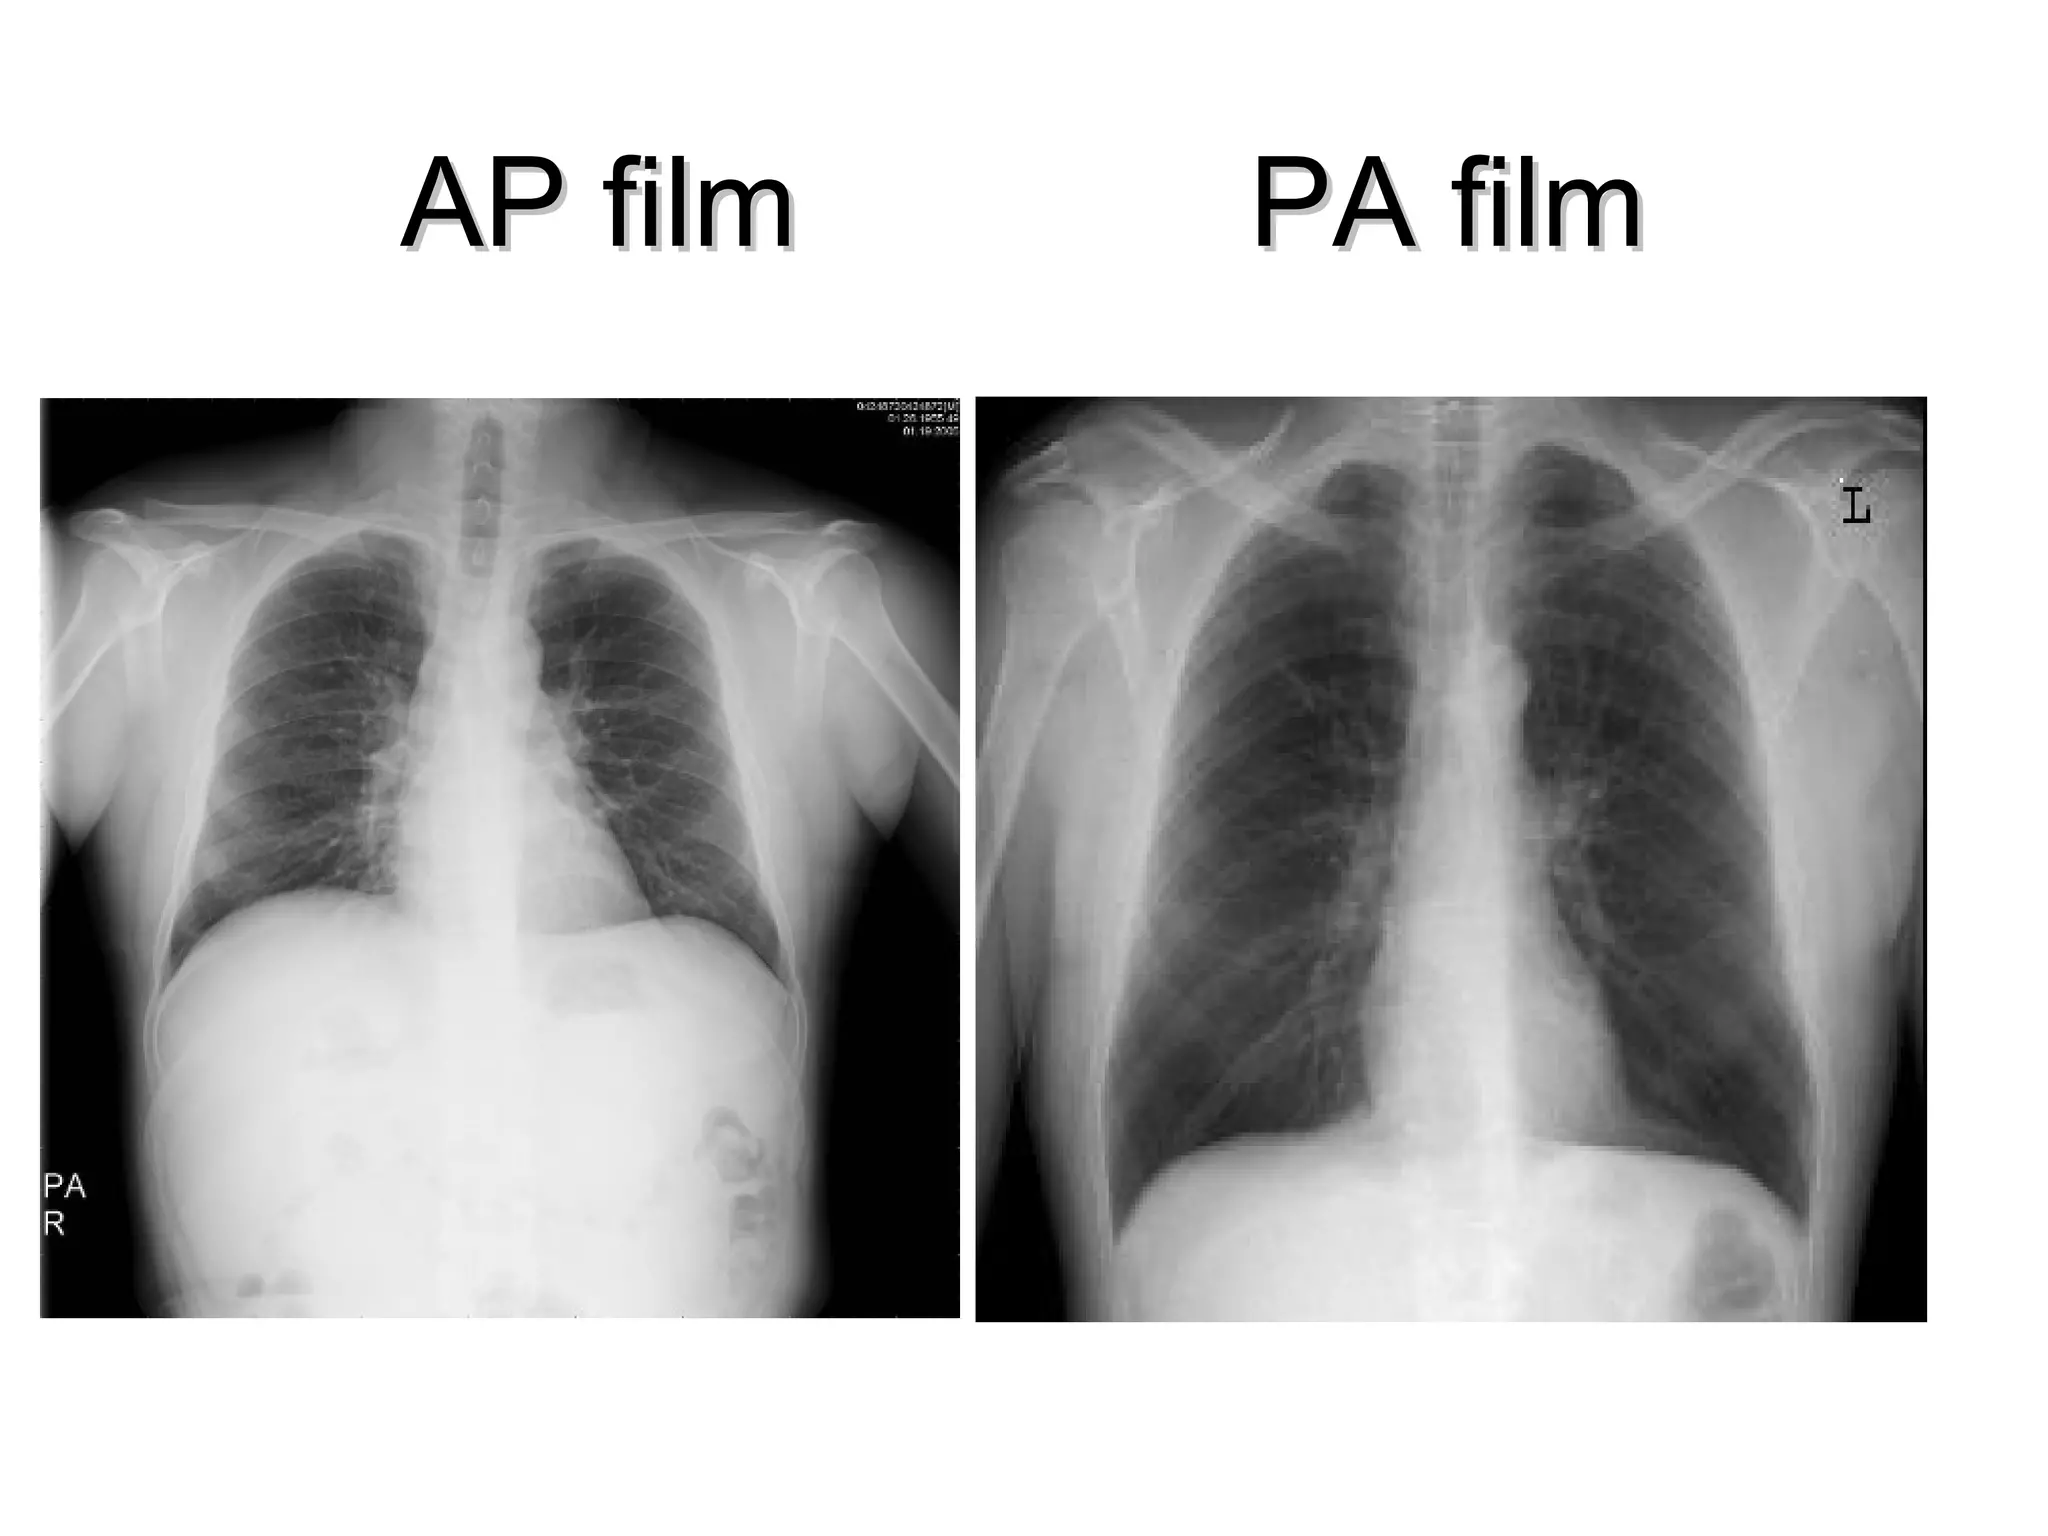

PA view                   AP view

• The posterior chest wall

is well shown

• The scapulae overlie the

upper lungs and the

clavicles are projected

more cranially over the

apices

• The neural arches are   • The disc spaces of the

visualised                lower cervical spine are

more clearly seen

AP film   PA film

PA view AP view • The posterior chest wall is well shown • The scapulae overlie the upper lungs and the clavicles are projected more cranially over the apices • The neural arches are • The disc spaces of the visualised lower cervical spine are more clearly seen

Viewing the PAFilm Technical aspects Centering Penetration the vertebral body and spaces should be just visible through the cardiac shadow. Degree of inspiration on full inspiration the anterior ends of 6th ribs or the posterior ends of 10th are above the right hemidiaphragm.

The mediastinum andheart The central dense shadow seen on PA CXR comprises the mediastinum, heart, spine and sternum The cardiac shadow lies to the left of the midline and 1/3 to the right although it is quite variable The transverse cardiac diameter normal for female < 14.5 cm and for males < 15.5 cm. The normal cardiothoracic ratio is < 50% on PA film and < 60% in AP film. An increase in excess of 1.5 cm in the transverse diameter on comparable serial films is significant.